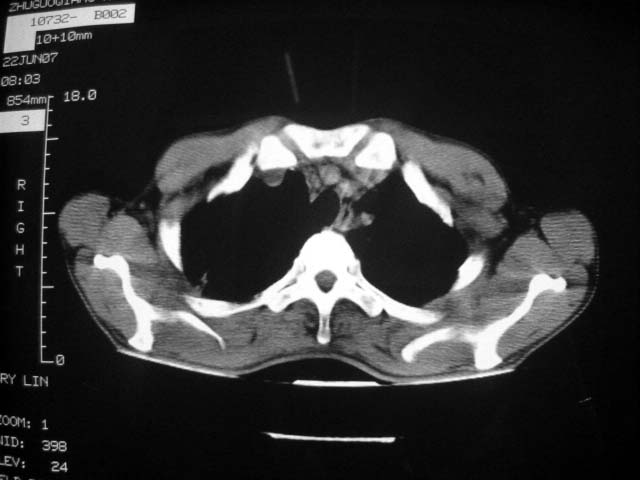

从ct7988c 至今未用任何抗生素及抗痨药,维持保肝治疗。患者低热、咳血渐消失。

07年6月22号复查

前几次大家认为是转移癌,但此次复查病灶却明显吸收好转,不支持诊断。请大家讨论。[emb10]

患者现无咳嗽咳痰及咳血,肝功好转,血清白蛋白降低,球蛋白升高,白球比小于0.5.少量腹水。

根据前后片比较应该考虑迁徙性肺脓肿,回帖相差甚远是因为前后片变化太大出乎大家意料之外,这就是影象诊断要结合临床复查对比的必要性,

回顾既往片,病变明显吸收,缩小,未经治疗,不支持肺转移瘤,可能为肺结节病或韦格氏肉芽肿